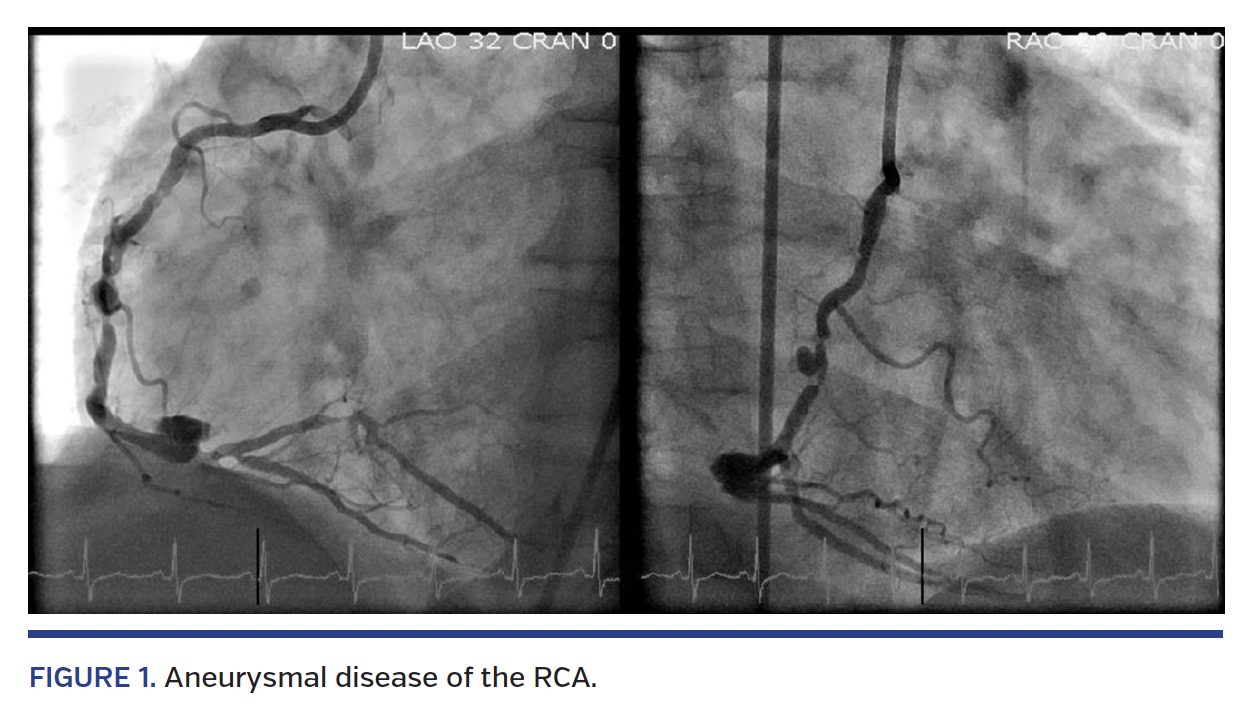

A 70-year-old man with hypertension, diabetes, chronic obstructive pulmonary disease, left ventricular ejection of 40%, and history of renal transplant presented to the emergency department with NSTEMI. Left heart catheterization revealed tandem 90% lesions of the RCA with adjacent, large saccular aneurysms (Figure 1; Videos 1 and 2). PCI was planned excluding the aneurysmal segments using Jostent GraftMaster PTFE-covered stents (Abbott Vascular). Given that the maximal length (26 mm) and diameter (4.8 mm) of the covered stents were felt to be insufficient for stable implantation into the aneurysmal segments, we planned on placing standard drug-eluting anchoring stents prior to GraftMaster implantation.